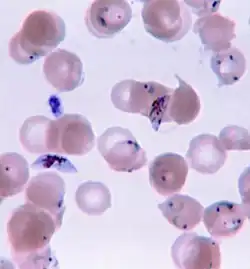

| O parasita Plasmodium ao atravessar o citoplasma de uma célula epitelial da fêmea do mosquito, na forma com que penetra no corpo do ser humano e de outros vertebrados. | |

A doença é geralmente transmitida pela picada de uma fêmea infectada do mosquito Anopheles.[2] A picada introduz no sistema circulatório do hospedeiro os parasitas presentes na sua saliva.[2] Os parasitas depositam-se no fígado, onde se desenvolvem e reproduzem.[1] Existem cinco espécies de Plasmodium que podem infetar os seres humanos.[1] A maior parte das mortes são causadas pelo P. falciparum. As espécies P. vivax, P. ovale e P. malariae geralmente causam formas menos graves de malária que raramente são fatais.[1][2] A espécie P. knowlesi raramente causa a doença em seres humanos.[2] O diagnóstico de malária tem por base análises microscópicas ao sangue que confirmem a presença do parasita ou através de testes de diagnóstico rápido que detectam a presença de antigénios no sangue.[1] Existem também técnicas de diagnóstico que usam a reação em cadeia da polimerase para detectar o ADN do parasita, embora o seu uso nas regiões onde a doença é endémica seja pouco comum devido ao seu elevado custo e complexidade.[5]

A malária é geralmente confirmada através de exame microscópico de esfregaços ou através de testes de diagnóstico rápido (DRT) baseados na deteção de antígenos.[44][45] A microscopia é o método mais comum na deteção do parasita.[46] No entanto, apesar do seu uso generalizado, o diagnóstico por microscopia tem duas desvantagens: muitos locais, sobretudo em meios rurais, não têm equipamento para a realização do exame e a precisão dos resultados depende da destreza do examinador e da quantidade de parasitas no sangue. A sensibilidade dos esfregaços varia entre 75–90% em condições normais, podendo diminuir até 50%. Os testes de diagnóstico rápido disponíveis são mais precisos a determinar a presença de parasitas da malária do que a análise microscópica, embora a sua sensibilidade e especificidade dependam do fabricante e não sejam capazes de determinar o número de parasitas.[46]